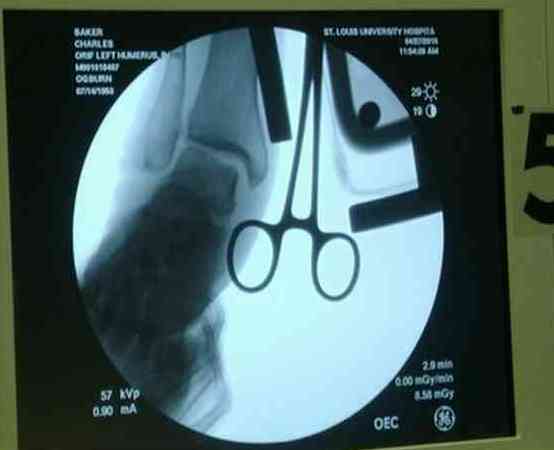

Впечатления об американской ортопедии. По проторенной коллегами дорожке в апреле по приглашению доктора Кульджанова Д., мы, 2 врача из казахстанской провинции -Канат Тезекбаев и Чертковер Григорий \ака Антон Андрианов\ провели 2 недели в университетской клинике города СентЛуис, Миссури. В прошлом году Никита Заднепровский, ранее побывав там, писал на форуме свои впечатления. Не желая повторяться, хочется довести до сведения коллег малую часть того, что нас поразило в США. Хотя одному из нас довелось поучиться три месяца в ФРГ по гранту АОАА и видеть клиники Швейцарии увиденное было ошеломляющим. Во-первых, подготовка врачей ортопедов длится 5-6 лет после колледжа, рабочая неделя их длится до 80 часов в неделю .Они –резиденты, закрывают все дежурства, прием пациентов. Опытные их учителя вызываются в ночное время по графику и очень многое резиденты делают сами под их контролем. Через пять лет к 33-35 годам он выходит самостоятельными врачами и ищут себе высокооплачиваемое место работы. Все стационары и амбулаторные приемы, частные или управляются частными компаниями, вся хирургическая служба высокодоходна и с врачами очень считаются, особенно по части приобретения заказанной ими техники. Экономическая целесообразность оставляет врачу только труд его квалификации, выписки, например, он диктует по телефону, мылом они летят в Индию, где дешевле труд машинистки, а к утру они уже в печатном виде у него в компьютере. Библиотека департамента ортопедии заставила утереть слезы доброй зависти, как и стопки журналов со всего мира на столе у профессора Кульджанова. Отсутствуют пленки рентгенограмм, доступ к сети с любого ПК, где хранятся все исследования пациента от поступления до амбулаторного этапа, интернет -до операционной. Удивительно крепок их командный дух, все дружно радуются быстро и удачно сделанной операции, бегут смотреть, что творится у коллеги, могут помыться на короткий момент для помощи и изучения, после идти продолжать свою работу. Еженедельные занятия с резидентами держат в информационном тонусе всех врачей. Можно много писать о работе приемного отделения, но те, кто видел сериал ER\Скорая помощь\ могут не сомневаться – на одного поступающего накидывается толпа врачей и персонала, а количество снимков и сканов МРТ и КТ не укладывается в наших головах. Правда о фильме они отзываются с иронией- фикшн, любовь на работе не крутим! Непререкаемый авторитет в клинике нашего куратора Джолдаса Кульджанова позволил нам свободно перемещаться по оперблоку и снимать операции. Активная хирургическая тактика при лечении политравмы, а именно таков состав пациентов, операции на нескольких сегментах позволяют избежать осложнений даже у престарелых . Так с д-ром Кулиджановым мы приняли участие в остеосинтезе перелома шейки, тибиального плато и предплечья у 92-летней дамы с протезом клапана, живущей на антикоагулянтах непрямого действия. Для выполнения операции анестезиологами путем переливания свежей крои и плазмы было создана на пару часов окно и операция была практически сухой. Вообще анестезиологи не выпячивают свою роль и с пониманием относятся к задачам ортопедов, вспоминается перл Илизарова- не больной для анестезиолога, а врач для больного\1982 год Курган\. Очень понравилась великолепная хирургическая техника всех докторов, крайне бережное отношение к тканями, практически не видели работы распаторами, минимально оголяется кость, используется инструментарий ЛОР и нейрохирургов. Орошение ран, джет- лаваж инфицированных ран проводится только физ.раствором. Многолетние наблюдения доказали состоятельность и даже к перекиси относятся критично -жжет ткани. ЭОП светит постоянно, даже измерение длины винта контролируется визуально, в их лексиконе нет слова СОЙДЕТ!Нет слов благодарности для Джолдаса, который опекал нас, как неразумных птенцов, часами сидел с нами перед монитором, ломая наши установки и пробивая косность совкового мышления. Те, кто уже бывал у него в гостях запомнили удивительный симбиоз полного западника с широкой восточной душой. Прилагаю несколько примеров изящной работы ортопедов из СентЛуиса.В первом случае у политравмированного пациента под ЭОП динамической пробой верифицирован разрыв МБС и выполнена фиксация позиционными винтами, 3.5 кортикальными.Кстати метчика в работе мы не видели, все винты self taping.Во втором случае у пациента с открытым многооскольчатым переломом дистального плеча на 4 сутки выполнен остеосинтез. Обратите внимание =доступ без резекции олекранона,медленная и ювелирная работа нетипичным для нас инструментом закончена полным восстановлением анатомии локтевого сустава.В небольшой дефект залит БМП\OP-1 Stryker ,продукт роста клеток человека в генной модификации\. Для профилактики гетеротопической оссификации ряд врачей применяют облучение на 2-3 сутки .Предвижу реплики скептиков - нам бы их зарплаты и оснащение, мы бы! Но для начала нам бы их учителей, их командный дух и их разумных рациональных организаторов!